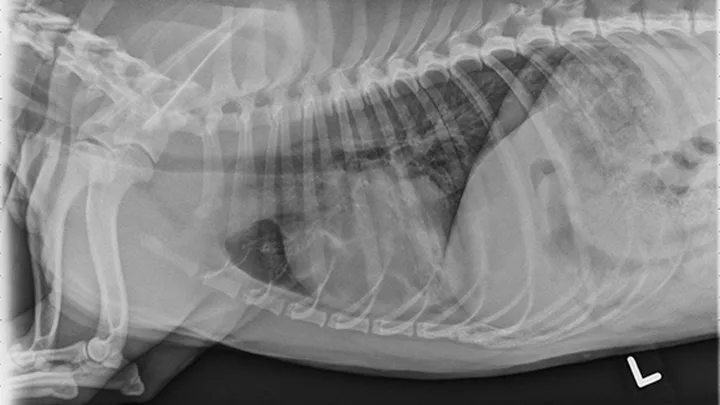

Image (right). Left lateral thoracic radiograph of a dog with bronchopneumonia secondary to B bronchiseptica infection. Note the patchy interstitial to alveolar infiltrates in the dependent portions of the right middle and left cranial lobes.